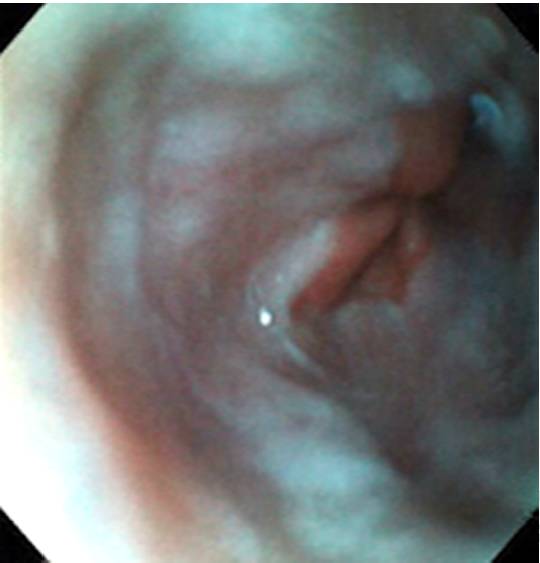

门脉高压是肝硬化的常见后果。约40-60%的肝硬化患者有食管胃底静脉曲张。基于曲张静脉的大小、肝硬化失代偿期和高危内镜特征存在,每年静脉曲张出血的发生率约5% -15%。

近期在线发表于Gastrointestinal Endoscopy杂志上的一项研究对一种非镇静作用、超细一次性胃镜(TDG)和常规胃镜检查(CG)在肝硬化患者食管胃底静脉曲张(GOVs)监测筛查中的作用与进行了比较。

CG在26例(54%)患者中确认了GOVs,其中10例(21%)有食管静脉曲张破裂出血的高风险(HROV)。与CG相比,TDG检测所有GOVs的准确率达到了92%,食管静脉曲张破裂出血的高风险(HROV)增加到100%。TDG检查中观察员间的一致性为88%(κ=0.74)。这使高风险GOVs增加到94%(κ=0.82)。没有严重的不良事件。

研究的结论是,非麻醉TDG是安全的,对GOVs的检查具有较高的诊断准确性和可靠性。基于临床的TDG的使用将使后续计划得以立即确定,使它对静脉曲张筛查和监测方案具有吸引力。